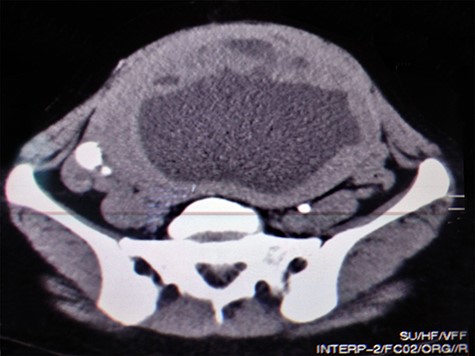

A 51-year-old woman (G 17, P 15, Ab 2) presented to the emergency department with low abdominal pain. Her gynecological history reveals pelvic pressure, irregular menstruation and menorrhagia during the past 3 months. She stated that all her pregnancies were delivered vaginally. Otherwise, neither her medical, surgical nor familial history was significant. At admission, her vital signs were in the normal range, she had mild pallor, she was afebrile and did not complain of nausea or vomiting. Her physical examination showed abdominal distention, enlarged uterine, equals to 20 weeks’ gestation. The remaining of her systemic examination was unremarkable. The patient’s laboratory tests showed microcytic anemia [RBCs: 4.42 × 106/ul, Hb: 11.2 g/dl, Hematocrit: 31.5%, MCV: 71.2 fl] and a slight increase in platelets count [403 × 103/ul] with normal white blood cell count. Her liver and kidney function were sufficient. Normal CA-125 and alpha-fetoprotein levels excluded any concerns about sarcomatous changes in leiomyoma; we were unable to perform the MRI and isoenzyme testing because they are high-priced investigations. Beta-hCG levels were normal, which exclude ectopic pregnancy. Doppler ultrasound was unavailable in our department; hence, we used normal ultrasound to rule torsion or rupture of any ovarian cysts. Both transvaginal and transabdominal ultrasound showed a large heterogeneous mass in uterine wall (Fig. 1). Pelvic CT scan reported an irregular mass measures 20 × 17 cm with central necrosis (Fig. 2).

Transvaginal ultrasound showing a heterogeneous mass in the uterinewall.